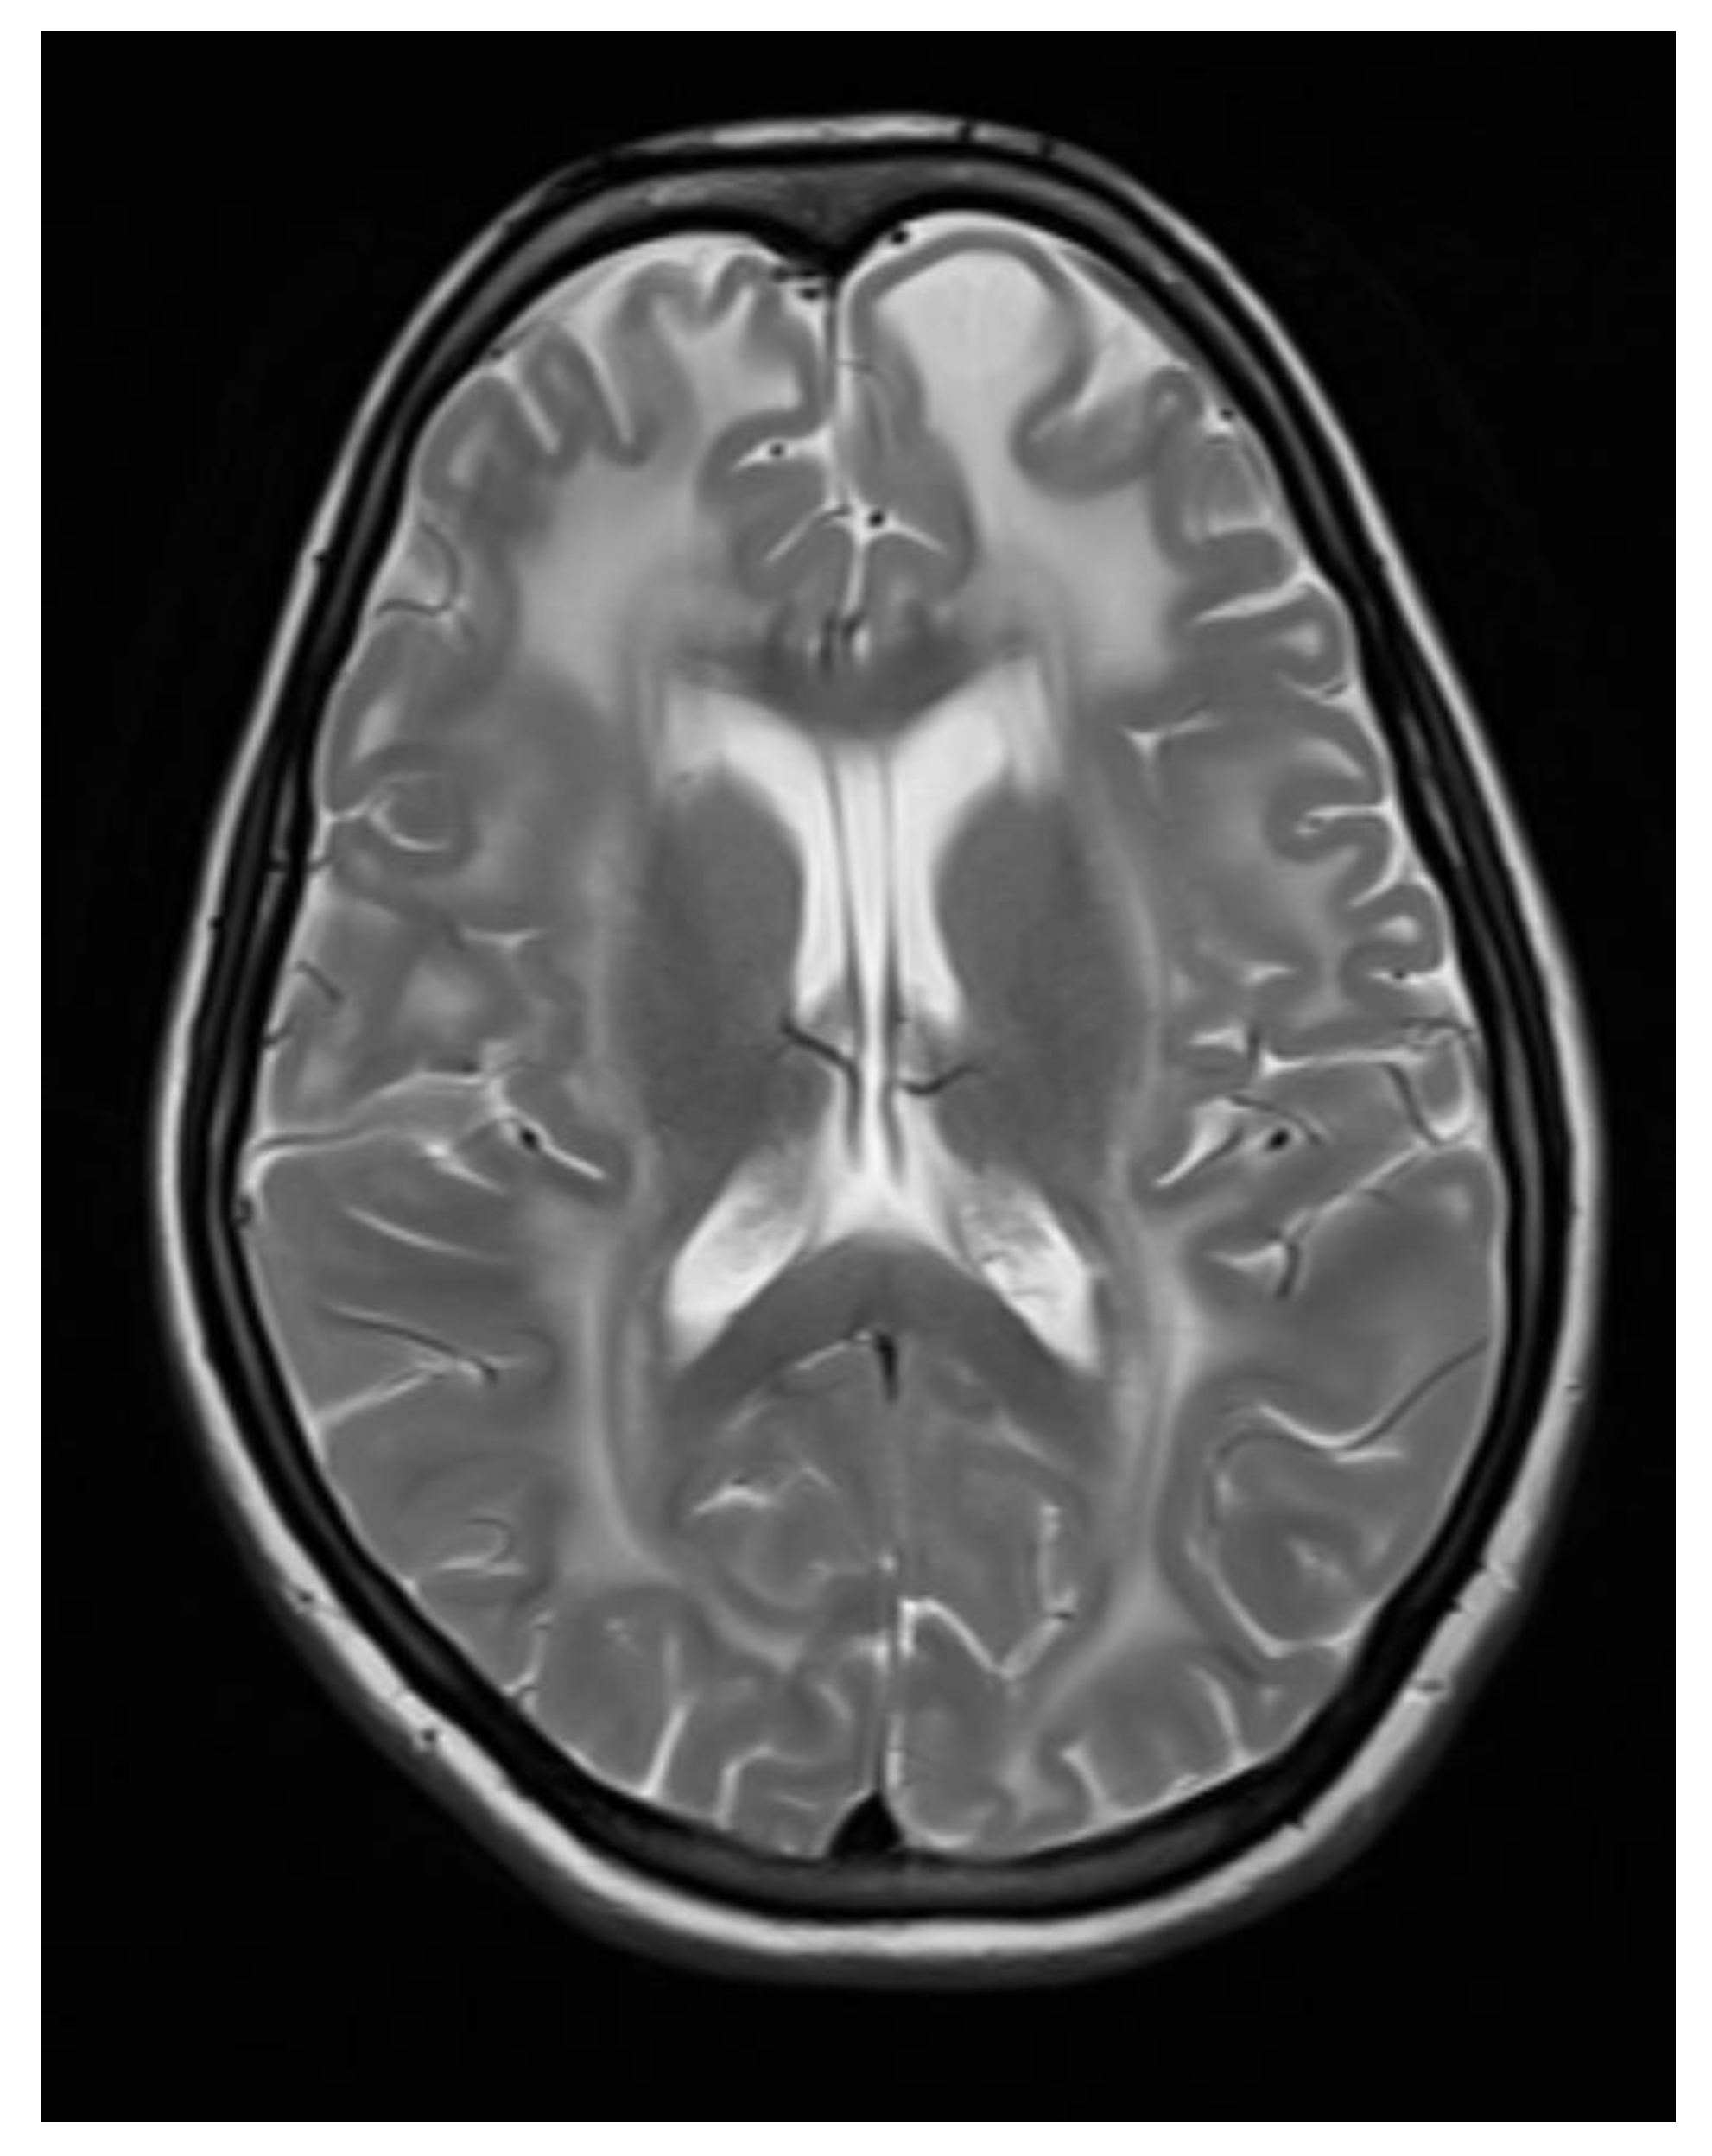

A contrast-enhanced MRI of the brain was performed, bilateral symmetrical diffuse abnormal T2WI/FLAIR hyperintensity involving the subcortical and periventricular deep white matter of bilateral cerebral hemispheres and corpus callosum with areas of diffuse restriction in bilateral centrum semi-ovale restriction, subcortical cysts, and cerebral atrophy were seen with possibility of Megalencephalic leukoencephalopathy with subcortical cysts also known as Van der knap disease. Post-contrast imaging showed normal enhancement, ruling out vascular abnormalities or abnormal enhancement patterns.

Figure 4. Axial T2 WI images showing Bilateral symmetrical white matter hyperintensity with subcortical cyst formation in the left frontal lobe.

The clinical and radiological findings were consistent with megalencephalic leukoencephalopathy with subcortical cysts, also known as Van der Knaap disease.